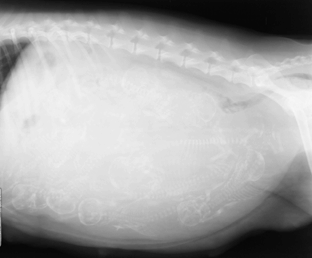

Водянка У Собак Симптомы Фото